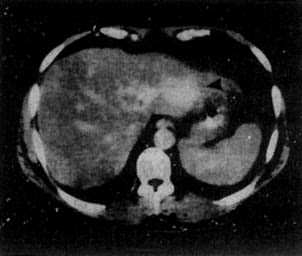

1.原发性肝癌 CT平扫绝大多数是低密度病灶,少数可以是低密度、等密度与高密度混合的病灶。肿瘤可以是单个或多个结节,也可呈巨块状。较大肿瘤因出血、坏死和囊变而致密度不均匀,中心部常出现更低密度区,其边缘部呈结节状。肿瘤边界多不清,少数边界清楚并有包膜。增强扫描肝癌区略有增强或不增强,而正常肝增强,因而使肿瘤境界更为清楚。癌变区可出现密度稍高的结节或隔,但其增强程度多不如正常肝。动态扫描时,即快速静脉注射造影剂并于开始注射后15~25秒内即行扫描,由于肝癌由肝动脉供血且供血丰富而迅速,而造影剂尚未到达肝内门静脉形成实质期,故肝癌结节可成为高密度,甚或显出高密度的异常肿瘤血管。但肝癌增强的时间较短暂,2~3分钟内即恢复为原来的低密度状态(图4-3-5)

图4-3-5 原发性肝癌

CT增强扫描,肝右叶有一较大圆形低密度肿块(↓),其边缘

部可见多个较密度的强化结节,其强化程度不如正常肝,中

心部仍为未强化的低密度区